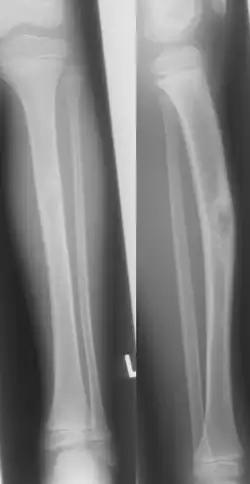

Jaffe-Campanacci-Syndrome, boy 7 Y, tibial bowing and cortical/subcortial mixed sclerosis

Jaffe–Campanacci syndrome is one of the disorders associated with café au lait macules (CALMs). Presentations may include intellectual disability, disseminated non-ossifying fibromas of the long bones and jaw, hypogonadism or cryptorchidism, or giant cell granulomas of the jaw.[2]